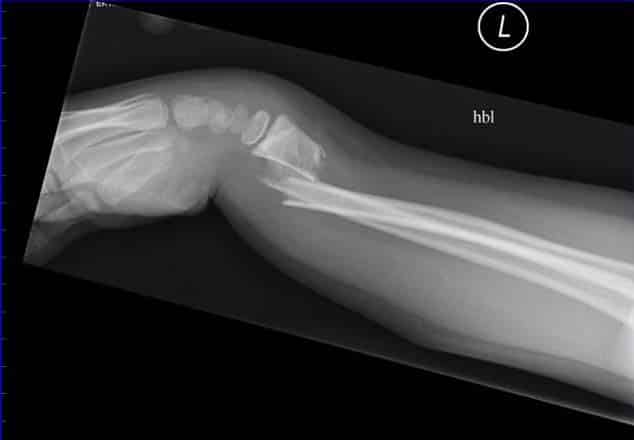

• Colles’ fracture – The most common type of radial fracture. A fall onto an outstretched hand causing a fracture of the distal radius. The structures distal to the fracture (wrist and hand) are displaced posteriorly. It produces what is known as the ‘dinner fork deformity’.

Fig 1.3 - Colles' fracture of the wrist. Note the 'dinner fork' deformity, produced by the posterior displacement of the radius.

Colles’ fracture of the wrist. Note the ‘dinner fork’ deformity, produced by the posterior displacement of the radius.